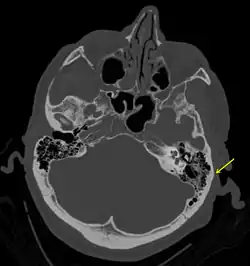

Симптом Бэттла (Бэттла признак) — кровоподтек (экхимоз) над сосцевидным отростком височной кости. Часто это единственный внешний признак базилярного (от лат. basilaris - основной, относящийся к основанию черепа) перелома черепа, чаще всего каменистой части височной кости.[1][2][3]

Признак Бэттла проявляется за одним или обоими ушами. Существуют определенные сложности для выявления данного симптома у больных с черепно-мозговой травмой. Его можно не заметить из-за волос. Кроме того, при оказании скорой медицинской помощи сразу после получения травмы данного симптома может не быть т.к. он обычно через 24-48 часов после перелома и может сохраняться в течение нескольких дней или недель.[4] При переломе костей черепа симптом Бэттла может сопровождаться гематомами вокруг глаз (симптом глаз енота), истечением ликвора из носа (ликворея), повреждением лицевого нерва, кровоизлиянием в полость среднего уха, а также угнетением сознания при тяжелой черепно-мозговой травме.[1]

Приложение достаточно большого усилия для перелома основания черепа вызывает появление кровоподтеков в области сосцевидного отростка из-за повреждения прилегающих к нему тканей.Также признак Бэттла может проявиться вследствие поступления крови из места перелома в область сосцевидного отростка.[8]